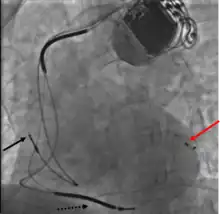

Les sondes auriculaire (dans l'oreillette) et ventriculaire droite sont posées suivant la même technique que pour un stimulateur cardiaque classique. La sonde ventriculaire gauche doit être positionnée, sous scopie dans le sinus coronaire (correspondant au réseau veineux du système vasculaire coronarien. Il s'abouche dans l'oreillette droite un peu en dessous de la valve tricuspide). La mise en place de cette dernière est l'étape la plus longue et délicate. Les sondes de stimulation ventriculaire gauches sont spécifiques. Elles sont en général préformées en queue de cochon par exemple pour assurer une relative stabilité dans la veine. Certaines peuvent être « tractées » sur un fin guide d’angioplastie pour progresser dans le réseau veineux souvent tortueux et fin. Il est impossible, du fait des variations anatomiques de garantir un taux de succès d’implantation de 100 %. Celui-ci est estimé dans les différentes séries entre 85 et 90 %. Éventuellement, d’autres techniques peuvent être proposées, par voie chirurgicale par exemple.

Le bon positionnement des sondes est vérifié par une radiographie ainsi que par l'électrocardiogramme qui doit montrer un affinement des QRS. Ce positionnement est important pour avoir le meilleur résultat possible. Ainsi l'écart entre les deux sondes (ventriculaire droite et gauche) doit être maximal[10]et la sonde ventriculaire gauche doit éviter d'être mise en position apicale[11].